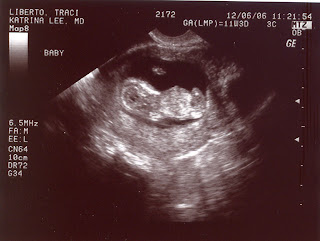

Wednesday, December 6, 2006

We had another appointment today and got to see the baby again. The baby is 11 weeks, has a heartbeat of 156 and is measuring around 1 1/2 inches long and weighing in at a quarter of an ounce.

11 weeks